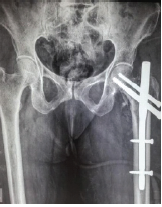

Management of Geriatric Acetabulum Fracture – A Case Report